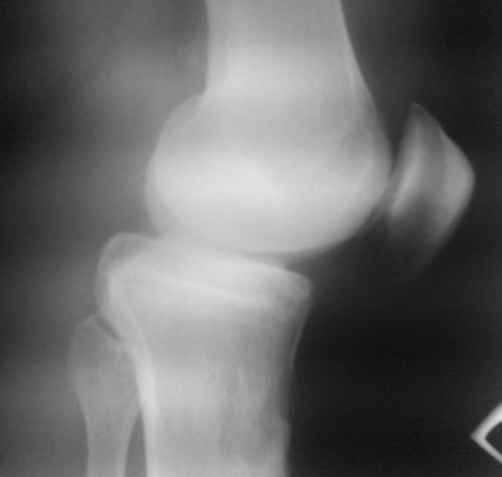

Доктора, предлагаю обсудить клинический случай. Мужчина 1960 гр в возрасте 10-12 лет получает травму, которую сейчас описать точно не может, не помнит.

В настоящий момент единственная, как ни странно, жалоба – появление кисты Бейкера. А еще больше косметический дефект. Собственно, с идеей коррекции косметического дефекта пациент к нам и обратился.

По видимому, тогда было повреждение задней крестообразной связки, рекурвация голени стала устойчивой, плато имеет неправильный угол наклона, а в верхней трети большеберцовой кости формируется маршевый перелом.

Объективно. Боли при пальпации нет, движения практически в полном объеме. Рекурвация внешне совершенно очевидная. Положение голени устойчивое.

Растущая киста Бейкера говорит о начале декомпенсации со стороны сустава, как я понимаю.

Что мы можем предложить пациенту. Ваши прогнозы по развитию маршевого перелома. Стоит ли сейчас предлагать коррекцию рекурвации. Что делать с «задним выдвижным положением», ибо это уже не «ящик». Нет даже колебания вперед-назад.

простите, мне и самому кажется, что качество снимков не лучшее.